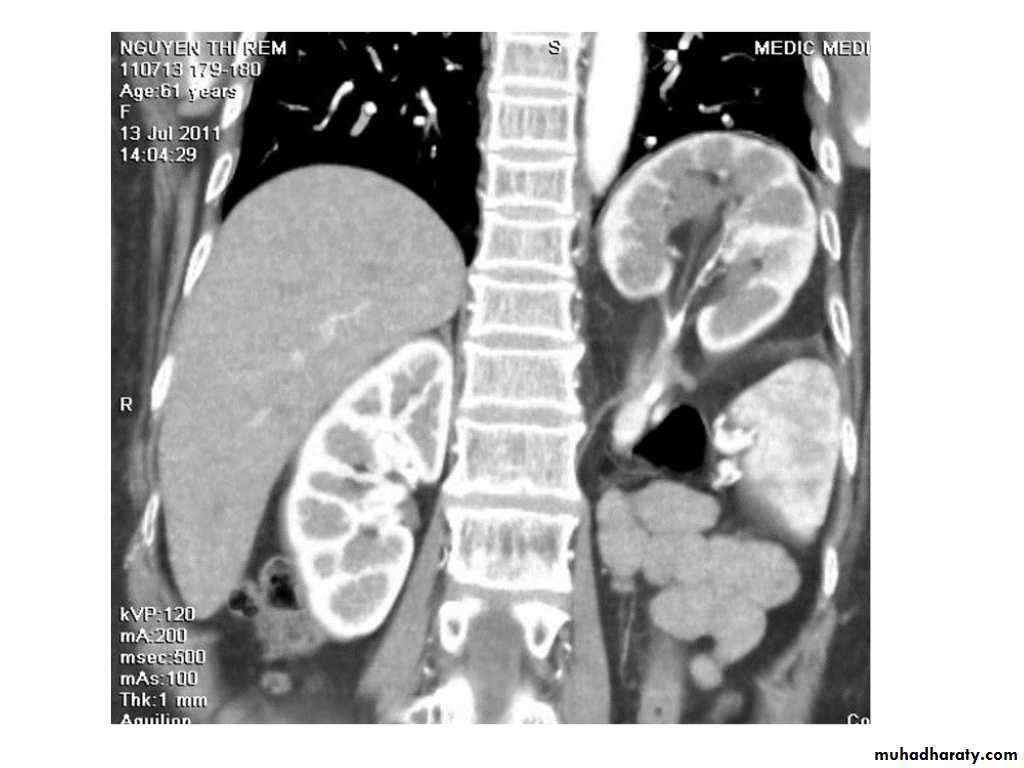

IVU shows

1. The kidneys at low position .2.Close to the spine with long axis parallel to the spine

3. Malrotation manifested by medially directed calyces.

4- The renal pelvis and ureters are anterior and lateral in position.

5- Hydronephrosis and calculi highly associated.